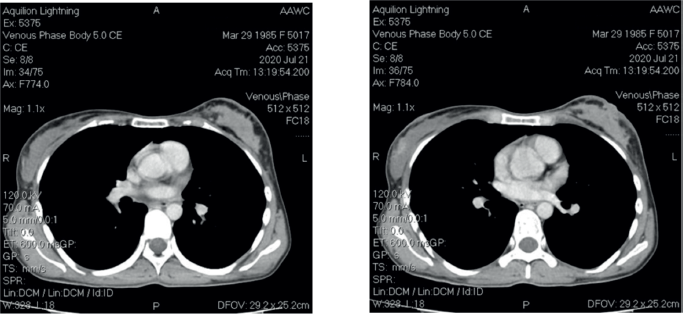

After four cycles, a mammogram revealed local recurrence in the left breast and a new lesion in the right breast (BI-RADS-3) with axillary lymphadenopathy on both sides. CT scan demonstrated total disorganisation of the left breast with skin thickening and a new suspicious lesion in the right breast (Figure 1). No distant metastases were observed.

Figure 1. CT scan images.